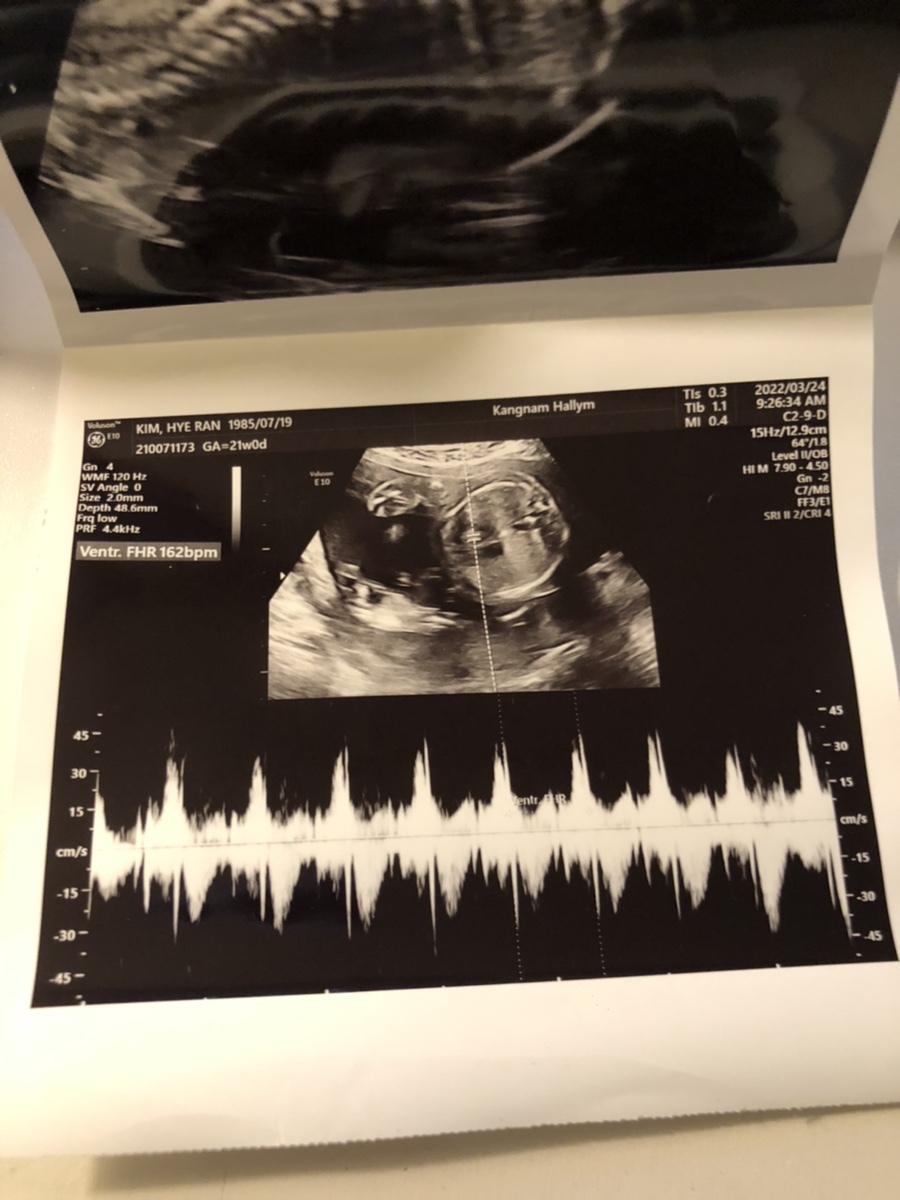

FHR(Fetal Heart Rate, 심장박동 수): 162bpm

초음파를 보는데 활발하게 뱃속에서 움직이던 이안이, 복부 초음파랑 질 초음파를 볼 때마다 본인 귀찮게 하지 말라는 건지 발길질을 해대는 게 선명하게 초음파 상으로 보인다. 이제 3주 뒤 임당 검사를 준비해 볼까나~